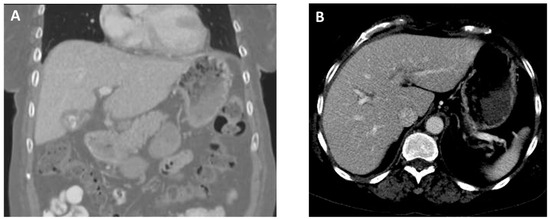

On arrival, she was found to be afebrile but tachycardic (116 beats per minute), tachypneic (26 breaths per minute), and hypoxic (SpO2 60–70% on room air). On physical examination, there was diminished air entry in the right lung and poor oral dentition, visualized with several loose or missing teeth along with visible tooth decay (dental caries). A complete blood count analysis revealed leukocytosis (25.57 k/µL; reference range, 4.50–11.00 k/uL). A comprehensive metabolic panel was unremarkable except for decreased carbon dioxide (14 mEq/L; reference range, 23–31 mEq/L). Elevated lactic acid (9.4 mmol/L; reference range, 0.5–2.0 mmol/L) and procalcitonin (10.05 ng/mL; reference range, 0.00–0.50 ng/mL) levels were detected. Chest X-ray imaging showed near-complete opacification of the right hemithorax. A computed tomography (CT) angiography of the chest revealed a large right hydropneumothorax with a leftward mediastinal shift (Figure 1A). The pleural fluid crossed the diaphragm, terminating in a thick-walled collection along the lateral aspect of the right lobe of the liver (Figure 1B). She developed progressive respiratory failure, requiring intubation and mechanical ventilation. The patient was administered intravenous (IV) vancomycin and piperacillin/tazobactam and was subsequently transferred to our facility for a thoracic surgery evaluation.

Figure 1. Images from computed tomography angiography of the chest obtained at admission. (A), Coronal view revealing a collapsed right lung due to a large pleural effusion (black arrow). (B), Axial view showing the presence of a perihepatic abscess (10.0 × 3.8 cm) (white arrow).